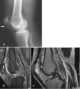

Healing fracture

Bone healing, or fracture healing, is a proliferative physiological process in which the body facilitates the repair of a bone fracture. Generally bone fracture treatment consists of a doctor reducing (pushing) displaced bones back into place via relocation with or without anaesthetic, stabilizing their position to aid union, and then waiting for the bone's natural healing process to occur. [Source: Wikipedia ]